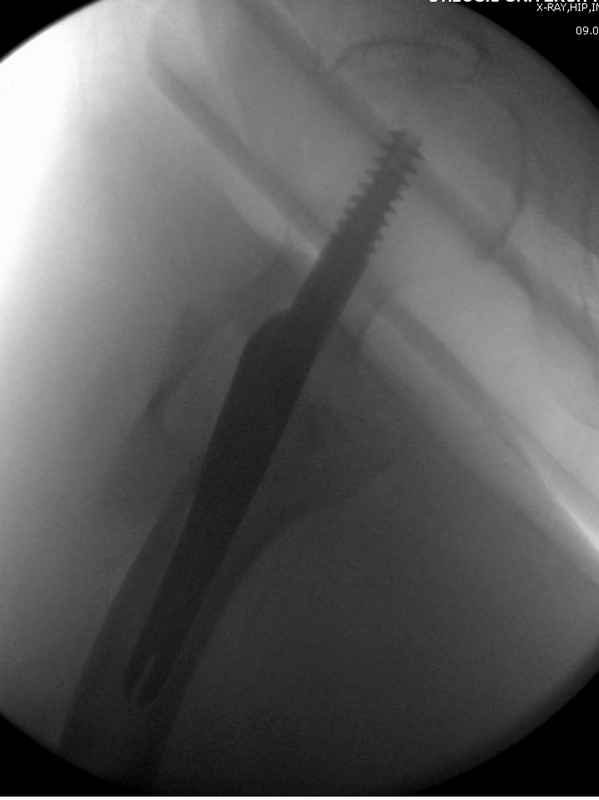

Re: Чрезвертельный перелом бедра

послал Djoldas Kuldjanov 25 Август 2009, 22:19

Здесь 83 года, травма в результате падения